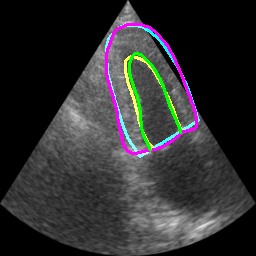

Table II displays the segmentation accuracy computed on the full dataset from patients having good and medium image quality ( patients) for the 4 algorithms described in section Sec. IV-D. Mean and standard deviation values for each metric were obtained from cross-validation on the 10 folds of the dataset. The values in bold correspond to the best scores for each metric. From these results, one can see that all the attention-based networks produced either the same, or better results than the baseline U-Net1, with AG-U-Net and LU-Net being the best performing models. Indeed, AG-U-Net obtained the overall best results for the segmentation of the LVEndo border ( value of mm and value of mm), leading to segmentation scores close but still higher than the intra-observer variability for this structure. The LU-Net-m5 approach obtained the best results for the segmentation of the LVEpi border ( value of mm and value of mm) and the lowest number of geometric outliers (%). Interestingly, these scores are either equivalent or lower than the intra-observer variability for this structure. It is also worth noting the robustness of the LU-Net model with respect to the choice of margin parameter, as margins of % and produce almost the same segmentation scores for all metrics. An illustration of the segmentation performance of the LU-Net-m5 network compared to the baseline U-Net1 model on three different cases is provided in Fig. 2.